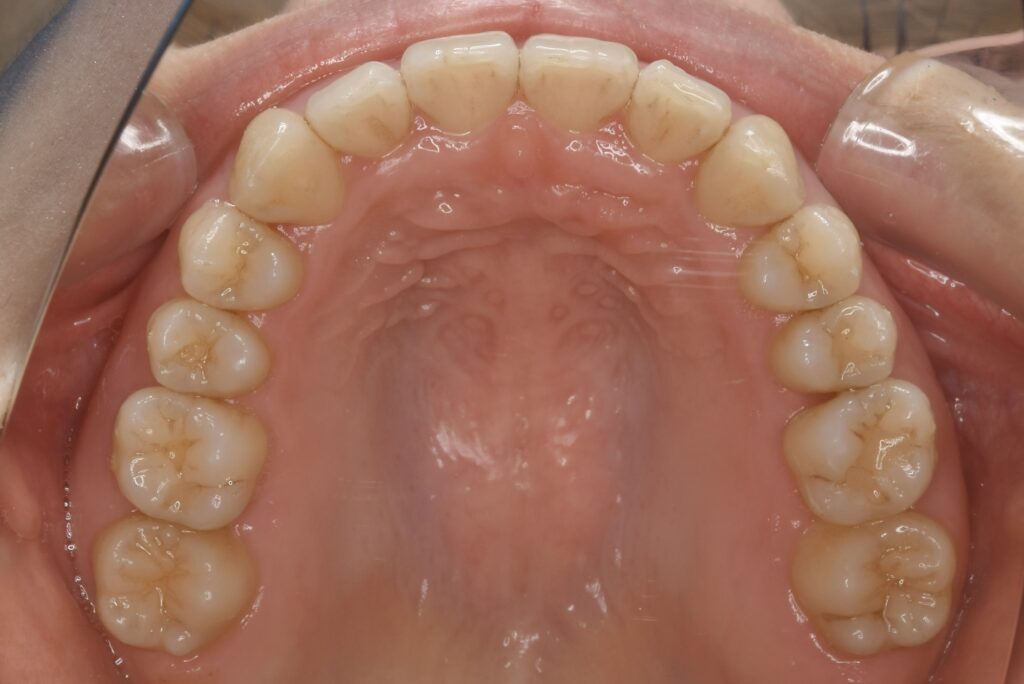

21歳 女性 治療期間:1年1ヶ月

叢生(ガタガタ)

マウスピース矯正装置(インビザライン)

BEFORE

AFTER

診断名・主な症状

叢生

治療内容

上下とも歯並びの横幅を広げながら、でこぼこを解消しました。

マウスピース矯正(インビザライン)

抜歯あり(智歯抜歯)

1年1ヶ月

10回

85万円程度(税別)

リスク・副作用

痛み、歯肉退縮、歯根吸収、抜歯に伴う出血や腫れが生じることがあります。